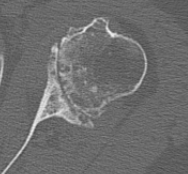

Type B3